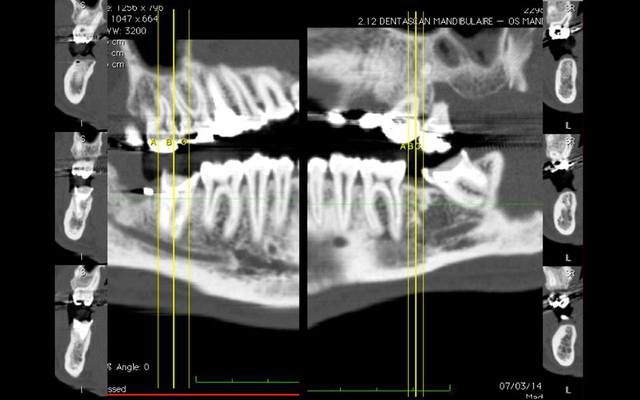

un petit test avec mon nouveau jouet

1) plâtre cône beam dans invesalius

2) cone beam vs cam3d

3) collage dans blender

4) résultat